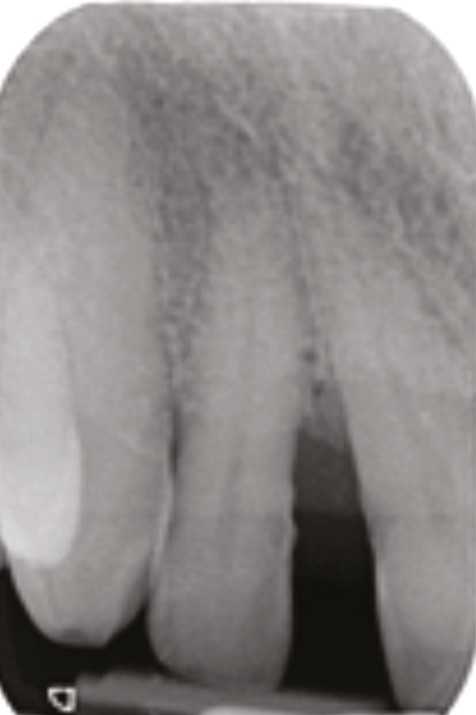

La migration dentaire pathologique est un déplacement dentaire provoqué lorsque l’équilibre entre les forces qui maintiennent la position physiologique de la dent et les forces qui tendent à la déplacer est rompu [1]. Selon la quantité de perte d’attache, de simples forces occlusales ou la poussée linguale lors de la déglutition suffisent à déplacer la dent.

La MDP est dépendante de l’axe des forces appliquées à la dent. Ces forces peuvent ainsi conduire à des déplacements horizontaux, des versions (basculement par rotation) et/ou des égressions/extrusions (déplacement vertical seul, souvent retrouvé lors de la perte de dent antagoniste).

Des combinaisons de mouvements sont le plus souvent retrouvées, notamment lors de la perte du calage postérieur : déplacement horizontal et vertical, migration « en éventail ».

L’étiologie des MDP est complexe et souvent multifactorielle. L’inflammation du parodonte (et son élargissement desmodontal), mais surtout la perte du ligament et de l’os alvéolaire dans lequel il est attaché, diminuent la solidité de l’ancrage et la résistance de la dent à l’impact des forces en présence :